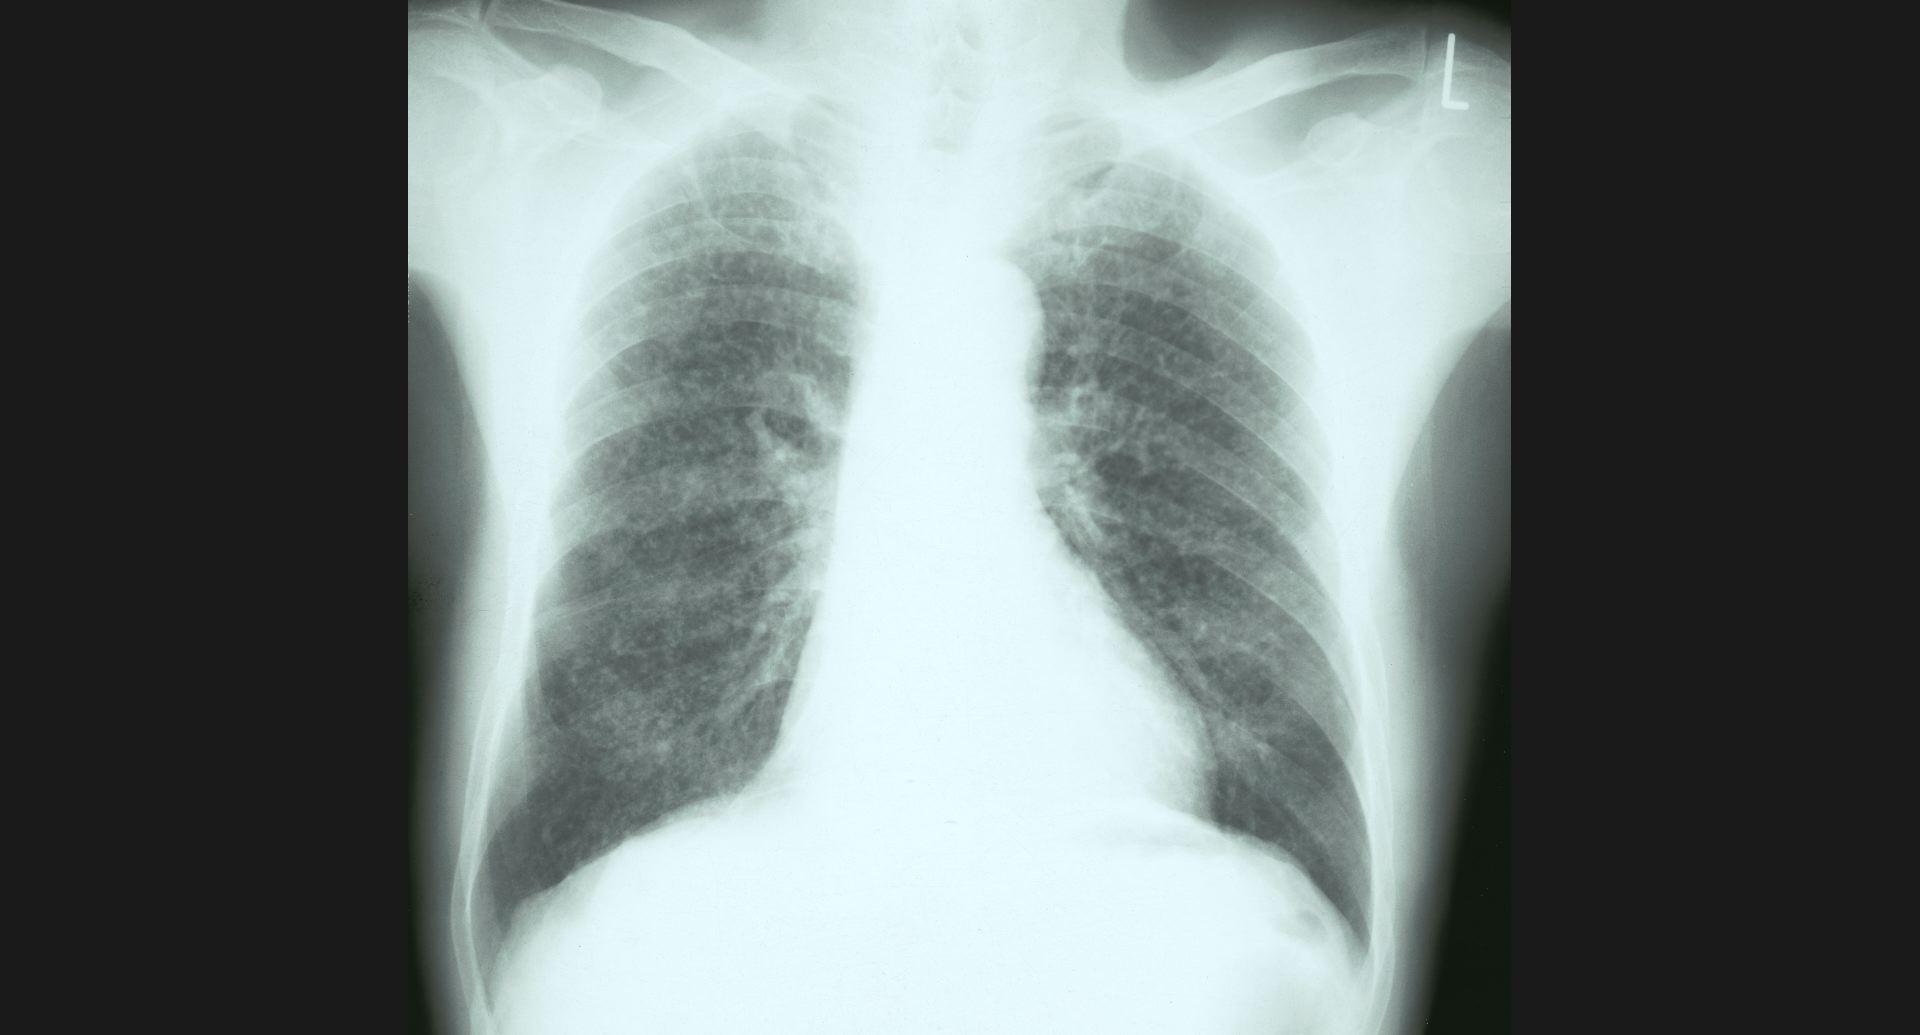

fig.9(94KB) :Pneumoconiosis

細かい斑状陰影。